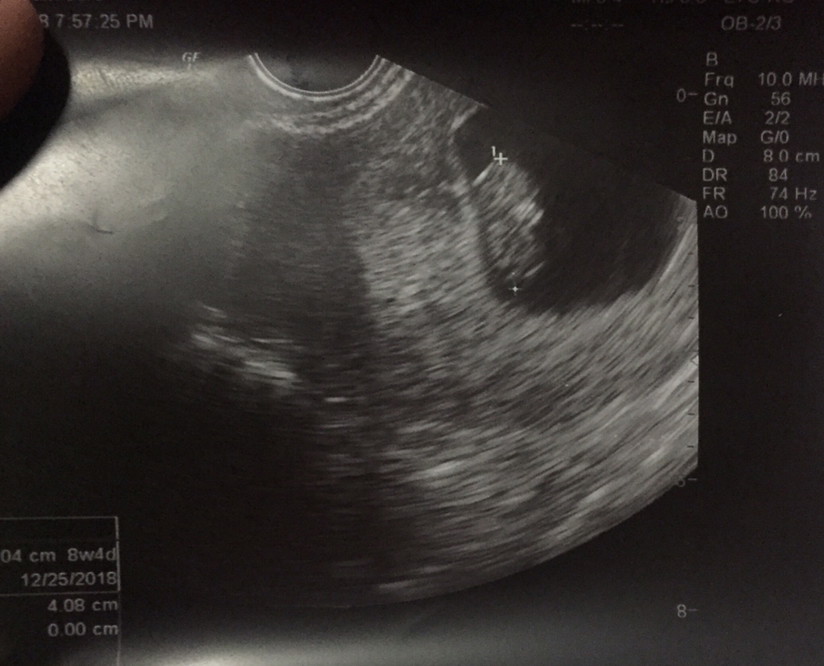

ขอดูใบซาวด์แม่เพศ ชาย หญิง หน่อยค่ะ

ชายค่ะ2เดือน

ได้ลูกชายคะ

ผู้ชายจ้า

เพศชายจ้า